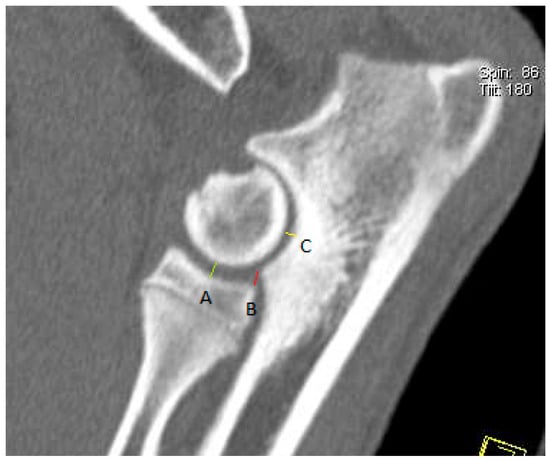

2.5. Measurement Techniques

3.1.2. CT Results of the Elbow Joints

3.2.2. CT Results for the Elbow Joints